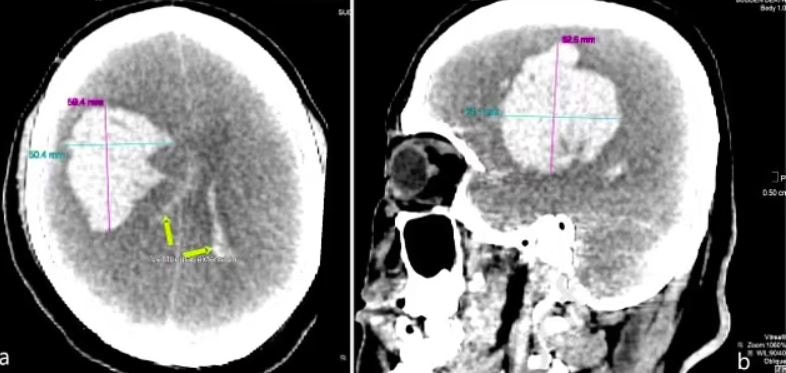

驗屍結果顯示,男子腦血管破裂出血,還有300克血塊,且死後測試血液酒精濃度達186.61毫克(每100毫升血液),超出英國酒後駕駛標準80毫克(每100毫升血液)一倍多,亦即超出香港酒後駕駛標準50毫克(每100毫升血液)兩倍多。

驗屍結果顯示,男子腦血管破裂出血,還有300克血塊。(網上圖片)